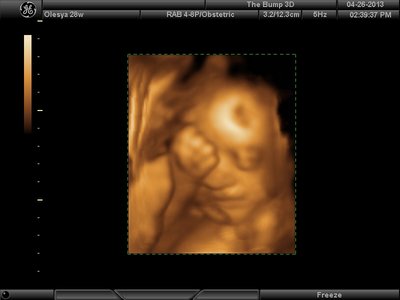

А я вчера на 3Д УЗИ ходила. Моя звезда закрывалась в еми 4мя конечностями. Просто пополам сложилась и спала себе сладко. УЗИстка провела со мной час, кое-как расшевелили маленькую, но ручка была постоянно на мордашке и засыпала она почти сразу снова. Я и на мяче прыгала и живот трясла. В конце более-менее фото вышли, но качество меня не порадовало. Возможно фри оф чардж еще раз переделают. Со средней фотки были отличного качества, а эти сплошное разочарование. Вот тут что-то более-менее еще. Главное пальчик оттопырила так смешно, мол минуточку. Вообще немного жутковатые фотки..хаха

| Вложения: |

image.jpg [ 47.86 КБ | Просмотров: 1458 ]

Еще одна, качество ужасное..

image.jpg [ 60.32 КБ | Просмотров: 1455 ]